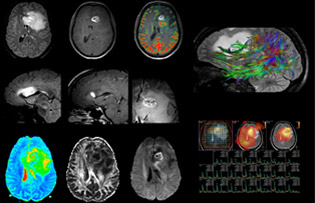

Dr. Savatovsky uses five or six different ExamCards for imaging a mass or a known tumor in the brain. “If there is a mass in the brain we try to characterize it to inform the neurologist for determining next steps or to help neurosurgeon prepare for a surgery or biopsy. For follow-up after treatment we have different protocols for different treatments and we adapt for intra- or extra-axial tumors.”

“The biggest challenges are properly characterizing the lesion and giving the surgeon all the information needed, such as the location of vessels and functional areas. Sometimes a very comprehensive exam is necessary, such as when a mass has been discovered at another hospital after which the patient is referred to us. We then do both lesion characterization and preoperative imaging in one exam, so both morphologic and functional assessment. For morphologic assessment we will use pre- and post-contrast T1-weighted imaging, FLAIR to assess infiltration, and diffusion. For functional characterization we will perform perfusion, spectroscopy, and susceptibility weighted imaging to look for micro vessels or micro hemorrhage inside the lesion[4]. For preoperative imaging we perform specific morphologic imaging that is compatible with the navigation system; depending on the location of the tumor, we would do fMRI or DTI.”

“That is the most comprehensive exam we would do. Ingenia has the good spatial resolution and high SNR to provide all this information, and the flexibility to use shorter sequences, so we can do a very comprehensive examination in a limited time.”